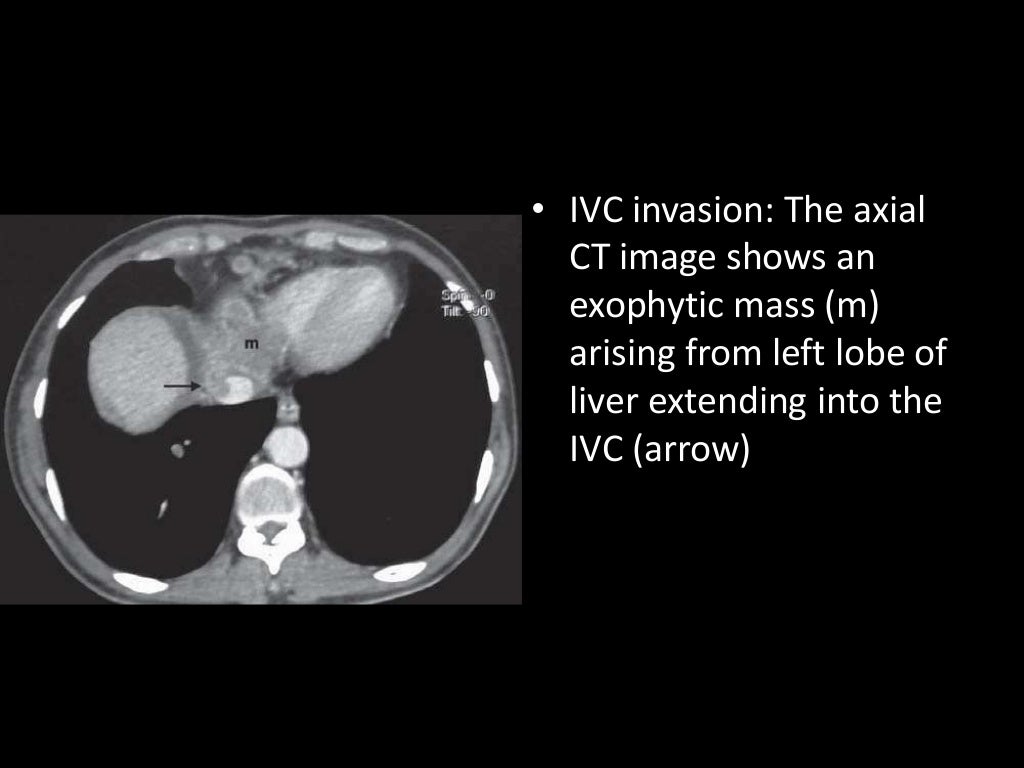

Imaging of Malignant Liver Lesions Malignant Medical Imaging Definition Imaging forms an essential part of cancer clinical protocols and is able to furnish morphological, structural, metabolic and. In contrast, tumors that stay localized and don't spread are called benign. A neoplasm is an abnormal growth of tissue that can be benign (noncancerous) or malignant (cancerous). A malignant tumor is a group of diseased cells defined by one of three. Malignant Medical Imaging Definition.

From www.slideshare.net

Imaging of Malignant Liver Lesions Malignant Medical Imaging Definition A malignant tumor is a group of diseased cells defined by one of three characteristics: Doctors use imaging tests to take pictures of the inside of your body. Benign tumors (noncancerous neoplasms) usually grow. In contrast, tumors that stay localized and don't spread are called benign. Radiologist yolanda bryce (right) and ultrasound supervisor van castor are part of a team. Malignant Medical Imaging Definition.

Imaging of Malignant Liver Lesions Malignant Medical Imaging Definition Imaging is able to spatially map key cancer features and tumor heterogeneity improving tumor diagnosis, characterization, and management. Imaging tests can be used to look for cancer, find out how far it has spread,. Uncontrolled growth, invasion and damage of healthy cells, or metastasizing (spreading) to. Doctors use imaging tests to help find and diagnose. Imaging forms an essential part. Malignant Medical Imaging Definition.